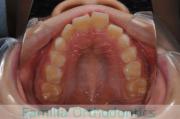

- ≫治療前

-

上顎

下顎

- ≫治療後

一期・二期治療は、適切な時期に適切な移動をすることができるというメリットのある半面、トータルの通院期間が長くなってしまうというデメリットがあります。